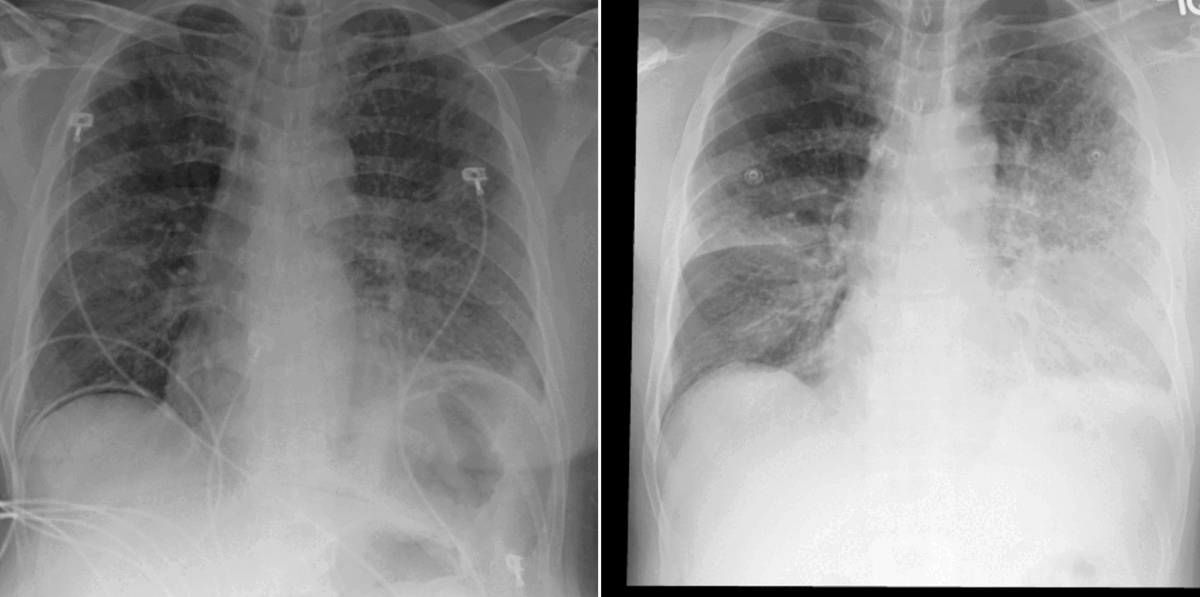

Two chest x-rays side-by-side animated with bounding boxes and attention maps on the affected area of the lung.

Figure 2: Example of current (left) and prior (right) chest x-ray scans. The attention maps computed within the vision transformer show (in purple) how the model interprets disease progression by focusing on these image regions. In this example, the airspace disease seen in the left lung lobe has improved since the prior acquisition.